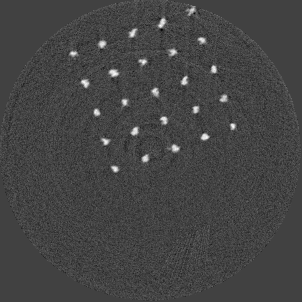

For the beam hardening study, we used Medipix All Resolution System (MARS) [12] containing a Medipix3RX ASIC with a 2 mm CdTe sensor bump bonded at 110 μ𝜇\mum in a single chip layout. All the acquisitions in this paper were carried out in CSM. The detector assembly is a module of the MARS camera which also contains a readout board, peltier cooling system and an integrated bias-voltage board. A negative bias voltage of -440 V was applied across the sensor during the acquisitions. The MARS scanner system comprises of MARS camera, a rotating internal gantry and an 80 kVp Source-Ray SB-80-1K x-ray tube (Source-Ray Inc, Ronkonkoma, NY) with a tungsten anode having 1.8 mm aluminium (Al) equivalent intrinsic filtration. The focal spot size is approximately 33 μ𝜇\mum [13]. Mechanical motor control (gantry rotation, source to detector translation, camera translation and sample translation), detector energy response calibration and threshold equalization were performed using the custom built MARS scanner software. The samples used in this study are shown in figure 2 and its description is provided in table 1.

Refer to caption

(a) Ti scaffold

(b) Mg scaffold

(c) Ti mesh

Figure 2: Snapshots of the metal samples (see table 1 for scale information).